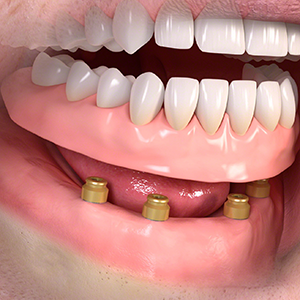

取り外しタイプ

(インプラントに義歯を固定します)

・2~4本のインプラントによって入れ歯を固定します。

全ての歯を失った。

インプラントを埋める。 (​2~4本)

インプラントに凸型の装置を装着。

義歯に付けた凹型の装置と接続させる。 義歯を自分で取り外して洗浄します。

インプラントオーバーデンチャー<ロケータータイプ> (沼津市在住 男性)

インプラントを埋め込み、固定用のロケーターを装着し、入れ歯をしっかりと固定する治療法です。

少ない本数でがっちり噛める治療法です。取り外し可能でしっかり固定できるので、入れ歯の誤飲の心配がなく、手入れがしやすいので寝たきりになっても安心に使用出来ます。

しっかり噛むことで踏ん張りがきくので転んで骨折するリスク回避にもなります。

● オーバーデンチャーを外した状態

● オーバーデンチャーを付けた状態